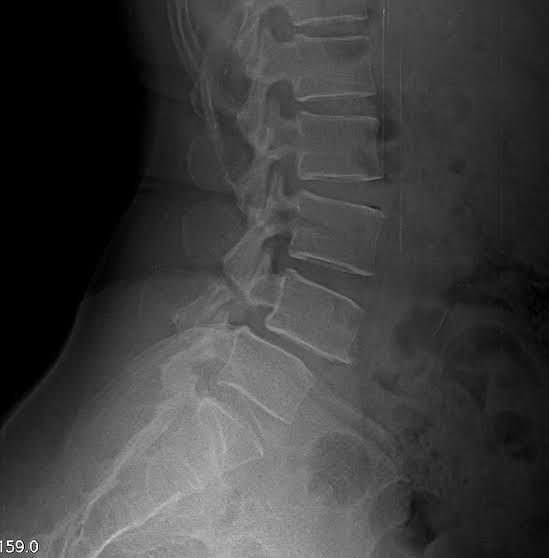

This Lumber plain x-ray shows forward slipping of L4 over L5 Leading to comprresion of the root L4 leading to loss of extension of Knee (Quadriceps femoris) and lost knee relfex with loss of sensation over medial calf,  medial malleolus and medial foot